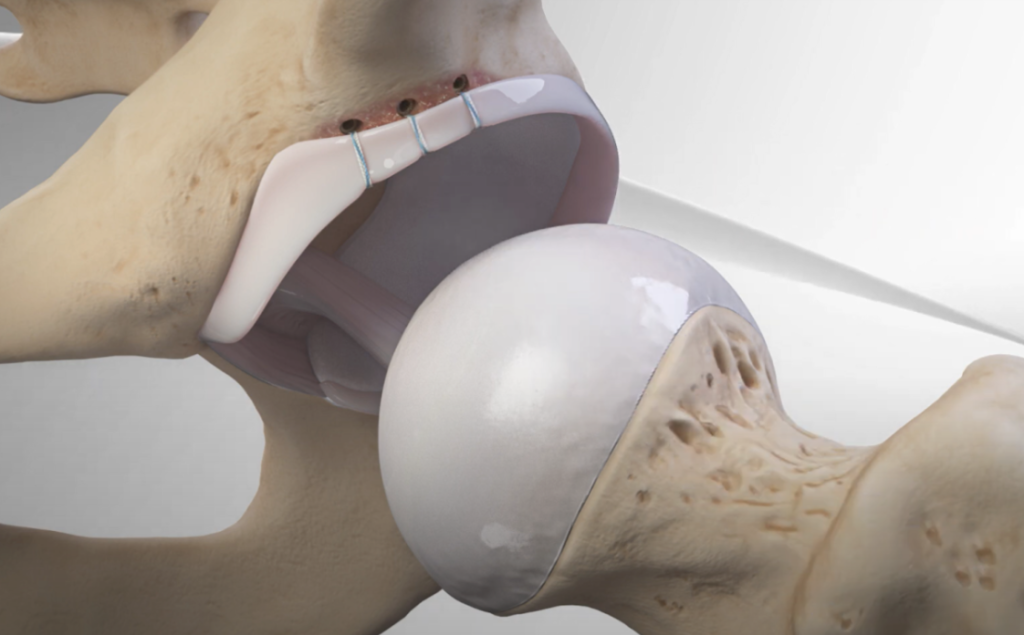

- Dans les cas plus graves ou lorsque les traitements conservateurs échouent, une intervention chirurgicale, telle que l’arthroscopie de la hanche ou une chirurgie de remodelage de l’os, peut être nécessaire pour corriger le conflit et réduire les symptômes.

Le traitement du conflit fémoro-acétabulaire peut prendre différentes formes. Les options incluent la chirurgie mini-invasive telle que l'arthroscopie, qui permet un retour plus rapide à la pratique sportive et présente un faible risque de complications. Une approche chirurgicale plus traditionnelle peut également être envisagée. Des séances de kinésithérapie visant à corriger les déséquilibres musculaires peuvent aider. Évitez les étirements, car ils peuvent aggraver le conflit. Parfois, des infiltrations d'anti-inflammatoires dans la hanche sont recommandées.

Le traitement d'un conflit de hanche dépend de la gravité des symptômes. Des approches non chirurgicales comme la kinésithérapie peuvent aider à corriger les déséquilibres musculaires. Cependant, les étirements doivent être évités, car ils peuvent aggraver la situation. En cas de besoin, des infiltrations d'anti-inflammatoires peuvent être proposées. Dans les cas plus sévères, une chirurgie mini-invasive (arthroscopie) ou une chirurgie classique peut être envisagée pour corriger le conflit.